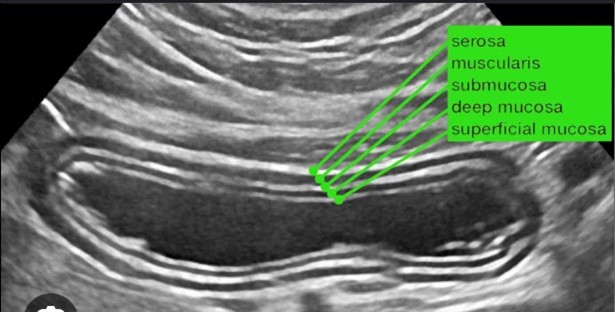

- POCUS en fibroscan in de kliniek

Dit onderwerp werd behandeld door een R. de Knegt, MDL-arts en opleider uit het Erasmus MC. Ik heb hem zowel nationaal als internationaal vaker gehoord. Hij houdt zich al jaren bezig met echografie en vooral de meerwaarde die dat geeft voor de MDL-arts. Naast leverechografie zijn ze onlangs gestart om ook darmechografie te onderwijzen. Met name dit laatste wordt behoorlijk aangemoedigd door de veel hogere vergoeding die men ontvangt ten opzicht van ons. Doordat echografie tegenwoordig zo goed is kunnen hierdoor het aantal scopieën gereduceerd worden. Veelal is de aandoening bekend, denk aan Cröhn of Colitis waardoor follow-up middels echografie volstaat. Al met al een goed verhaal met raakvlakken met de vorige voordracht.